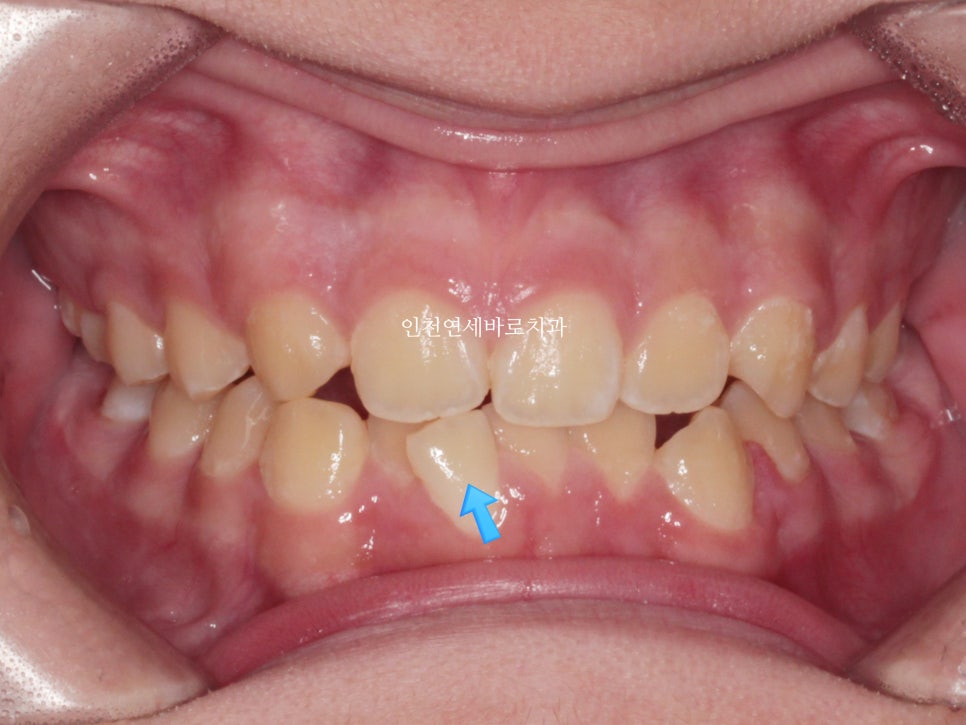

처음 우리병원 왔을때 사진입니다

여기 오른쪽 두번째 앞니가 없는것이 발견되었습니다.

얼굴 전체의 중심선과도 많이 벗어난 모습입니다.

위아래 치아끼리의 중심선은 안맞아도, 위치아의 중심선과 얼굴 전체의 중심선은 일치하는 것이 보기 좋습니다.